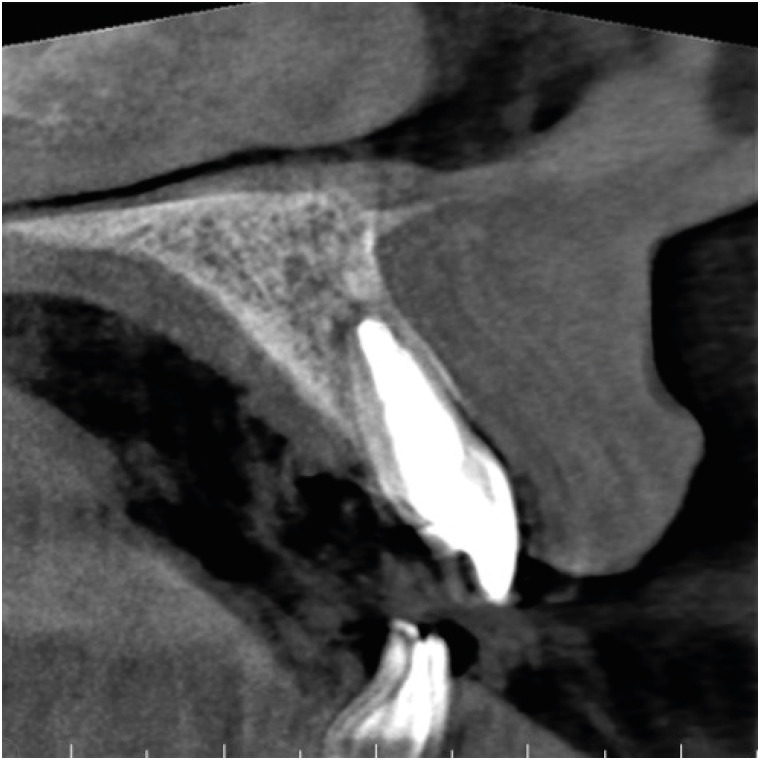

A follow-up CBCT scan was taken 1 year after the final root canal treatment and revealed continued healing of the periapical radiolucency and reformation of the buccal bony wall around the apex (Figure 5). The tooth has remained asymptomatic ever since, and the patient was satisfied with the result.

Figure 5

Follow-up cone-beam computed tomography scan taken 1 year after the finalization of root canal treatment, showing the homogeneity of the short-fiber reinforced composite inside the canal.